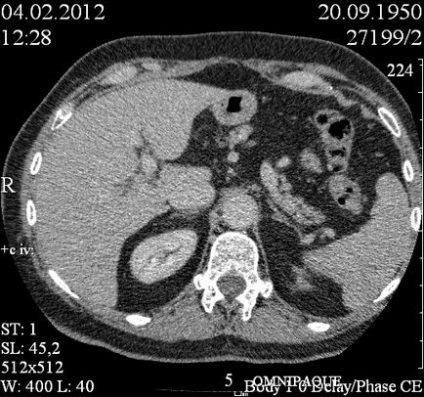

Kialakítása előtt a kontraszt tette rosszul, sűrűsége körülbelül 27 ed.N. Az artériás fázisa kontraszt nem halmozódnak, kivéve az egyik kamrában, amely felhalmozódik (Contrast, hogy ez a kandalló nem egyértelműen vizuliziruetsya feltehetően izodensiven).

A parenchymás felhalmozódnak fáziskontraszt. Képződmények a parenchyma csak körülbelül 6, beleértve a subcapsularis helyen. A szerkezet a homogén képződmények, kerek alakú, tiszta kontúrokkal.

5 perc elteltével Introducion kontraszt képződését izodensivny lép parenchyma. Egyes elszigetelt retroperitoneális nyirokcsomó méretig 6 mm.

OGC is végzett CT. Talált coelomic ciszta a szívburok. Mediasztinális nyirokcsomók vannak a nem kibővült. Becsült következtetés: multifokális lép limfóma, vagy metasztázis a lépben.

5 perc elteltével az adagolás után a kontraszt: